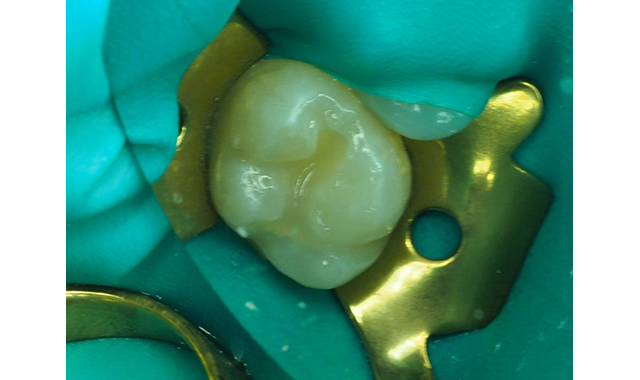

The decision was made to use the self-etch technique utilizing Tokuyama Universal Bond from Tokuyama Dental America, self-cured and self-etched truly universal adhesive. The Tokuyama Universal Bond adhesive Part A and B components were mixed together and then applied to the de-sensitized dentin and cut enamel (Fig. 6). Tokuyama Universal Bond, considered an eight-plus generation adhesive, was dried with gentle air for 5 seconds followed by 5 seconds medium air to evaporate the solvents, while no light curing was required.

Fig. 6 Mixing and application of Tokuyama Universal Bond, which is a self-cure universal adhesive.